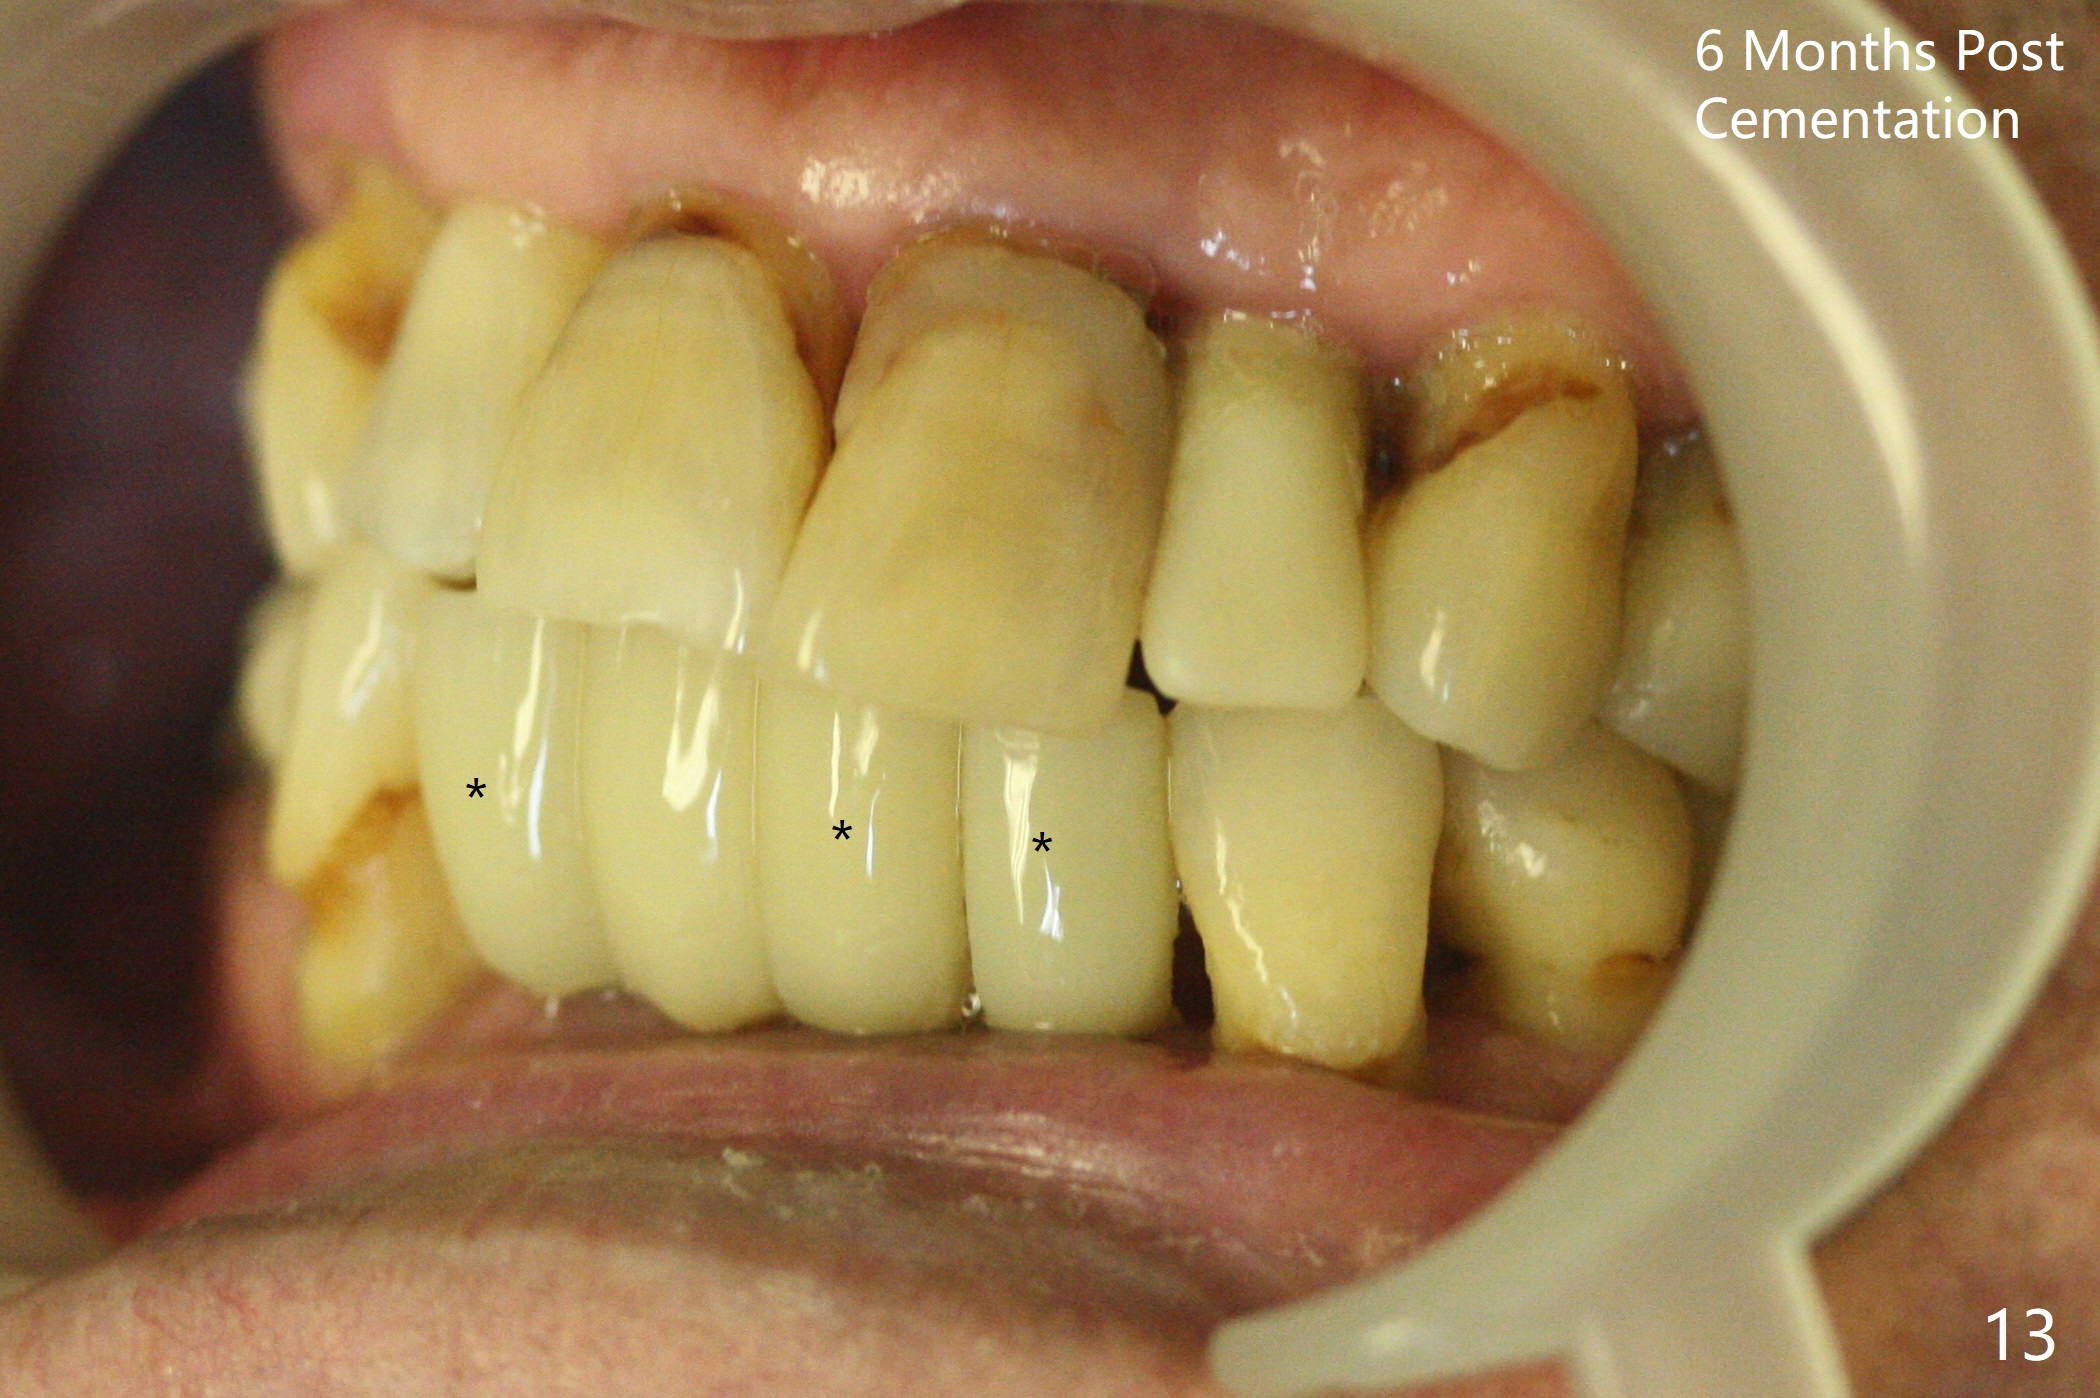

When the patient returns, the tooth #24 has exfoliated, while the ones at #25 and 26 has mobility III (Fig.1). The patient requests the tooth #23 extraction (Fig.2), but not #27. After SRP and extraction, osteotomy is initiated mesial to the sockets #23,25 and 26 (Fig.3,4) with intention to place 3 1-piece implants for 3 incisor crowns (Fig.5,6). Following Vanilla graft (Fig.5 *) a splinted provisional is fabricated to close the sockets (Fig.6). Peri-implant spaces close 5.5 months postop (Fig.7). Impression is taken after reprep for margin and parallelism (Fig.8). The final restoration consists of #23 single unit crown and #24-26 3-unit FPD (Fig.9). It appears that 2.5 mm 1-piece implants are not too small for the lower incisors (Fig.10-12), especially the central one (Fig.11). There may be perforation in the apical half of the lingual plate (L in Fig.10). The patient is not pleased with the shade of the #24-26 3-unit FPD (Fig.13 (6 months post cementation)). There is metal show through the abutments (*).